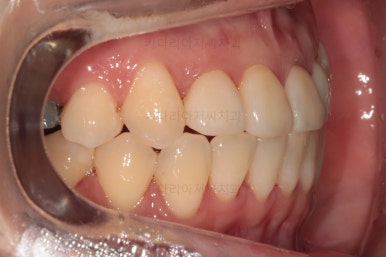

초진 시 입안의 모습입니다.

이미 썩어서 부러진 치아도 몇 개 보이고요.

많이 삐뚤어진 치아쪽은 양치가 힘들어 이미 많이 썩어 있는 상태에 덧니쪽은 잇몸도 많이 내려간 상태였습니다.

말그대로 교정치료 뿐만 아니라 전반적인 치료가 필요한 상황이었습니다.